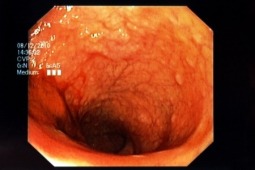

Perforacja jelita należy do najpoważniejszych powikłań kolonoskopii. Powikłanie to zdarza się...